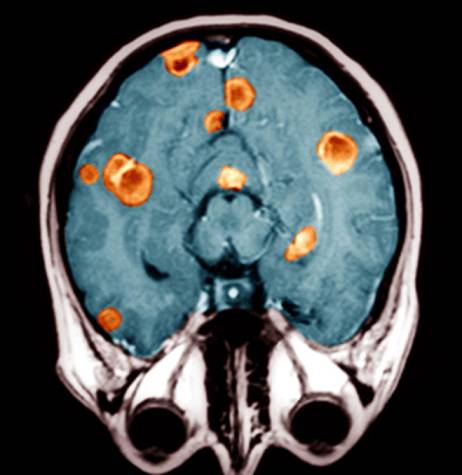

«Золотой стандарт» в диагностике метастатического рака головного мозга — магнитно-резонансная томография (МРТ). Во время этого исследования получают изображения внутренних структур тела, используя сильное магнитное поле. По снимкам врач может судить о количестве, размерах, расположении метастатических очагов.

При технически не удаляемых и чувствительных к противоопухолевым лекарствам видах рака, таких как молочная железа, мелкоклеточный рак лёгкого и герминогенные опухоли яичка, на первом этапе прибегают к химиотерапии, к которой в дальнейшем присоединяют облучение всего массива головного мозга. При радиочувствительных опухолях лечение можно начать с тотального облучения мозга. При опухолях не более 3,5 см и менее четырёх узлов как единственный метод эффективна стереотаксическая радиохирургия. К опухоли подводят с разных сторон несколько пучков радиоволн, они пересекаются в одном месте — там, где находится метастаз. В итоге раковые клетки уничтожаются, а окружающие здоровые ткани получают минимальную безопасную дозу. В комплексе с облучением мозга и химиотерапией результат лучше.

- МРТ ‒ золотой стандарт диагностики прогрессивных раковых опухолей в этих областях. В зависимости от вида вторжения, изменяется качество изображения.